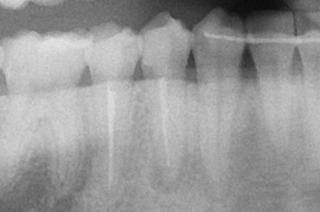

こちらは根充後のレントゲン。

次回は築造、レジンでおしまいです。(その後は経過観察ですね)

心なしか初診時の写真の時より、透過像が小さくなっているような気がします。

痛み、なくなるといいですね。